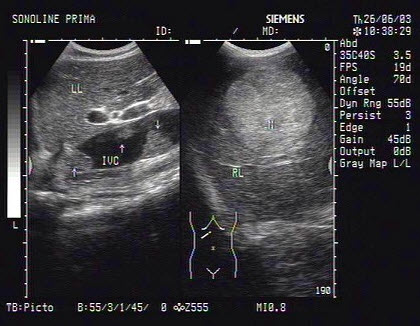

16、单项选择题

图中肝脏图像最长的管道为()

A.肝右静脉

B.肝中静脉

C.门静脉右支

D.下腔静脉肝段

E.门脉左支